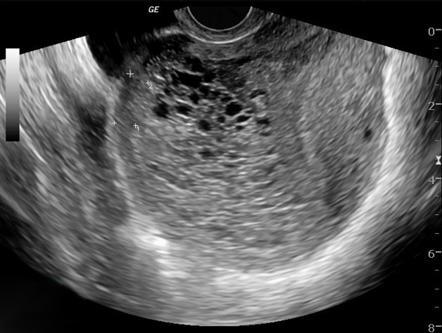

Appears as snowstorm on USS, with hydropic villi + large theca lutein cysts

USS - snowstorm appearance, large lutein cysts